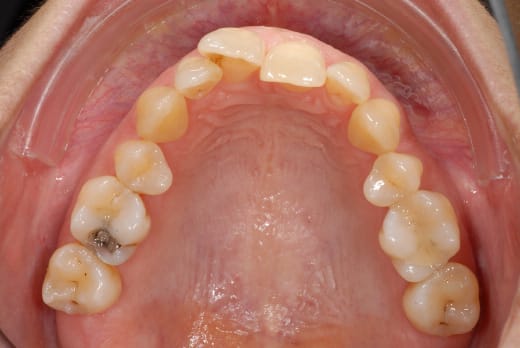

regardez-moi cette 11 qui fout le camp...la 21 complètement palato-versée...je vous raconte pas les guidages...

bon puisque vous n'avez pas trop de patience, je vous l'envoie le haut, allez zou....

j'ai pas encore la photo avec l'espèce d'appareillage tout or :-)